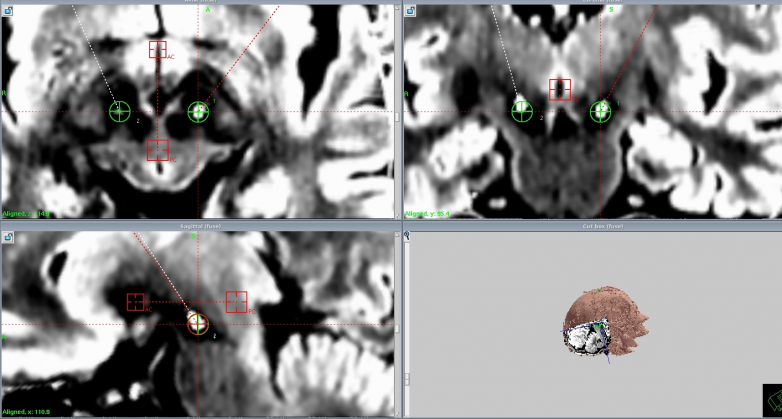

計偉主任帶領手術團隊,以精湛的技藝和嚴謹的態度投入到手術操作中。他們借助先進的影像導航技術,精準定位核團靶點,每一個操作都小心翼翼、精準無誤。在植入設備的過程中,手術團隊密切配合,精細操作,確保電極準確無誤地植入到預定位置。整個手術過程緊張而有序,手術最終順利完成。術后患者各項生命體征平穩,神志清醒,肢體活動良好,顱腦CT及各項檢查均未見異常,手術取得了圓滿成功。